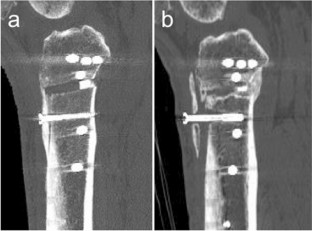

All patients who underwent DTO were retrospectively reviewed, and 104 successive patients were included. The Knee Society Score and complications including tibial tubercle fracture were recorded. On radiographs and computed tomography scans, the length, thickness, width, height, and bony union of the osteotomized tibial tubercle and the posterior tibial slope were statistically analysed.

Fracture of the tibial tubercle occurred intraoperatively in 11 patients (10.6%) and in the postoperative period in 1 (1.0%). The case of postoperative fracture showed non-union. There was no significant difference in the Knee Society Score between the non-fracture and fracture groups. There were significant differences in the posterior tibial slope and the height of the tibial tubercle between the groups (p < 0.0001 for each comparison). The logistic regression analysis showed that the height of the tibial tubercle was associated with a higher risk of the fracture of the tibial tubercle (p < 0.01; OR, 1.548; 95% CI, 1.149–2.085). However, there were no significant differences in the bony union rate of the tibial tubercle at 6 months after surgery between the groups.

Tibial tubercle fracture did not affect the clinical outcome and bony union in spite of the relatively high occurrence rate. Anatomical risk factors for the fractures was a lower tibial tubercle position.